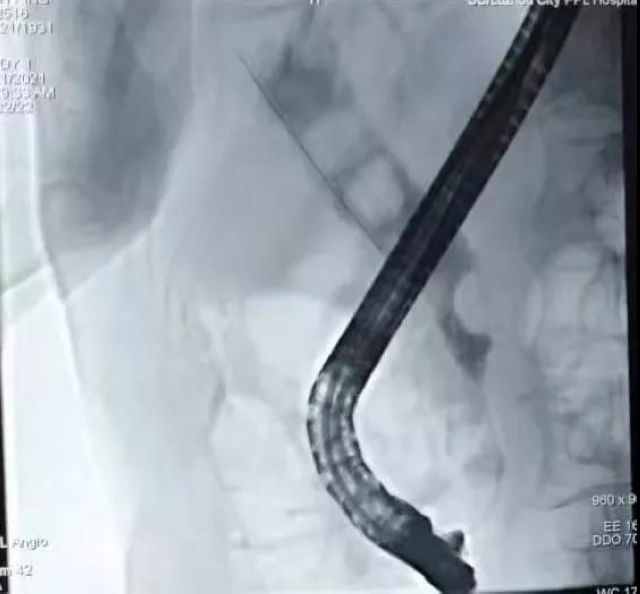

突破极限!泸州市人民医院为2名九旬老人实施ERCP取石术

近日,多名高龄患者因无法耐受常规手术,经多方咨询,专门到我院肝胆胰脾·血管外科寻求ERCP治疗。91岁林奶奶因胆总管结石,反复胆道感染已先后7次住院治疗,患者及家人经多方咨询后来到泸州市人民医院肝胆胰脾·血管外科寻求ERCP治疗;90岁李爷...